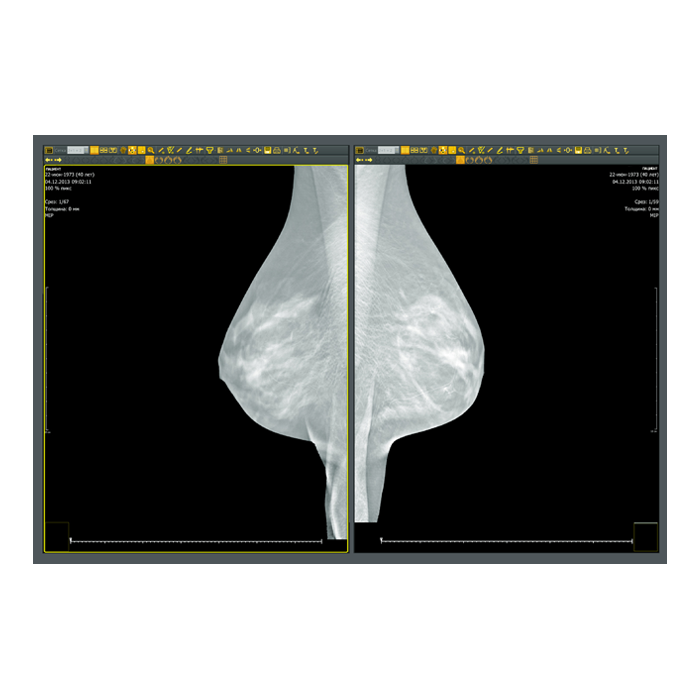

- Рентгенология